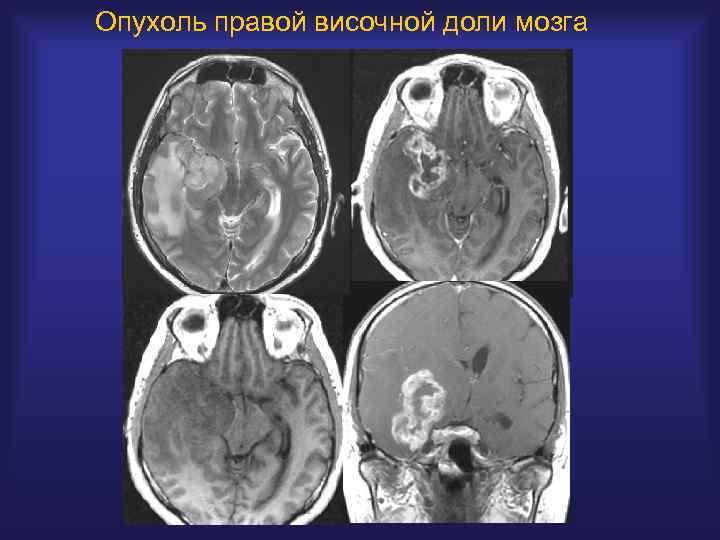

Опухоль правой височной доли мозга